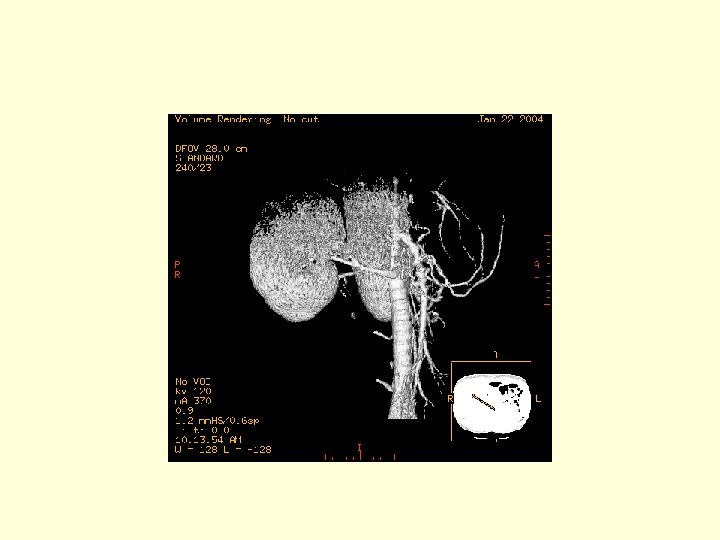

This is a 3 D image showing the branches of the SMA.